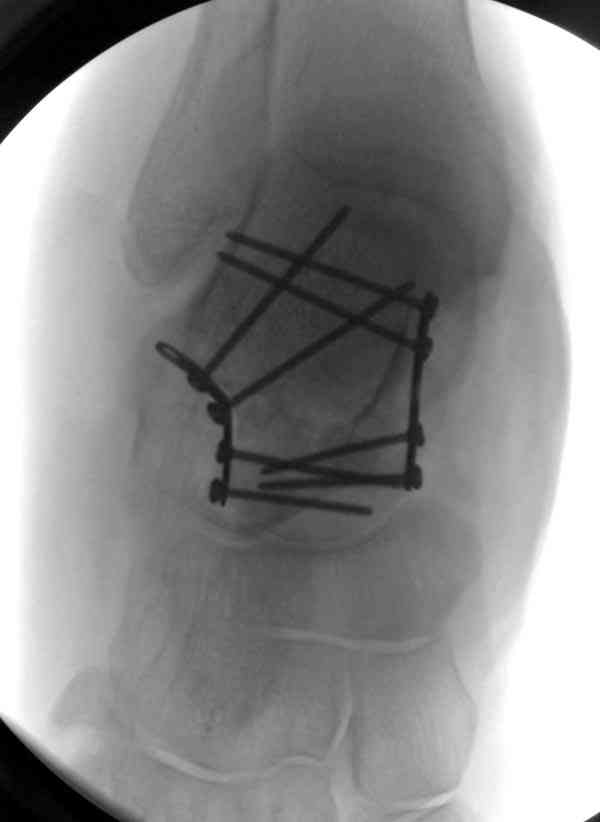

Случай с множественным оскольчатым переломом тарана оперированный из двойного доступа.

Через 2 мес.:

Через 8 мес.:

Через 14 мес.: